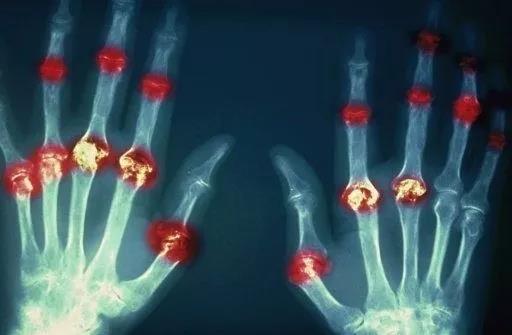

? 類風濕關(guān)節(jié)炎

類風濕關(guān)節(jié)炎是一種高度致殘的自身免疫性疾病,發(fā)病十年的患者中至少有50%的人失去勞動能力。

類風濕關(guān)節(jié)炎©Health Same of Flickr

1977年,Baldwin在用骨髓干細胞移植治療再生障礙性貧血的過程中,意外發(fā)現(xiàn)患者的類風濕關(guān)節(jié)炎得到緩解。

2004年,歐洲骨髓移植和抗風濕病聯(lián)盟對60例類風濕病關(guān)節(jié)炎移植患者進行回顧性分析,這些患者的關(guān)節(jié)破壞都達到不可修復(fù)程度,生活不能自理,通過干細胞移植治療后,67%的患者得到明顯緩解。

我國國內(nèi)多家醫(yī)院已開展了干細胞治療類風濕性關(guān)節(jié)炎的臨床研究。首例自體干細胞移植治療類風濕關(guān)節(jié)炎在北京協(xié)和醫(yī)院完成。經(jīng)過5個月隨訪,這些經(jīng)常規(guī)藥物治療失敗且病情發(fā)展迅速的患者,在接受干細胞移植治療后,癥狀均獲得改善,關(guān)節(jié)腫脹消失,各項檢查指標恢復(fù)正常。

解放軍323醫(yī)院2011年的一項臨床研究中,27位患者(對照組)只使用藥物治療;另外153位患者(細胞治療組)在藥物治療的基礎(chǔ)上進行臍帶間充質(zhì)干細胞輸注。結(jié)果顯示,治療組DAS28、HAQ 評分、ACR20較對照組下降明顯(分值越低,療效越好),Th1/Th2趨于平衡、Treg升高與臨床實驗指標及癥狀的緩解直接相關(guān)。